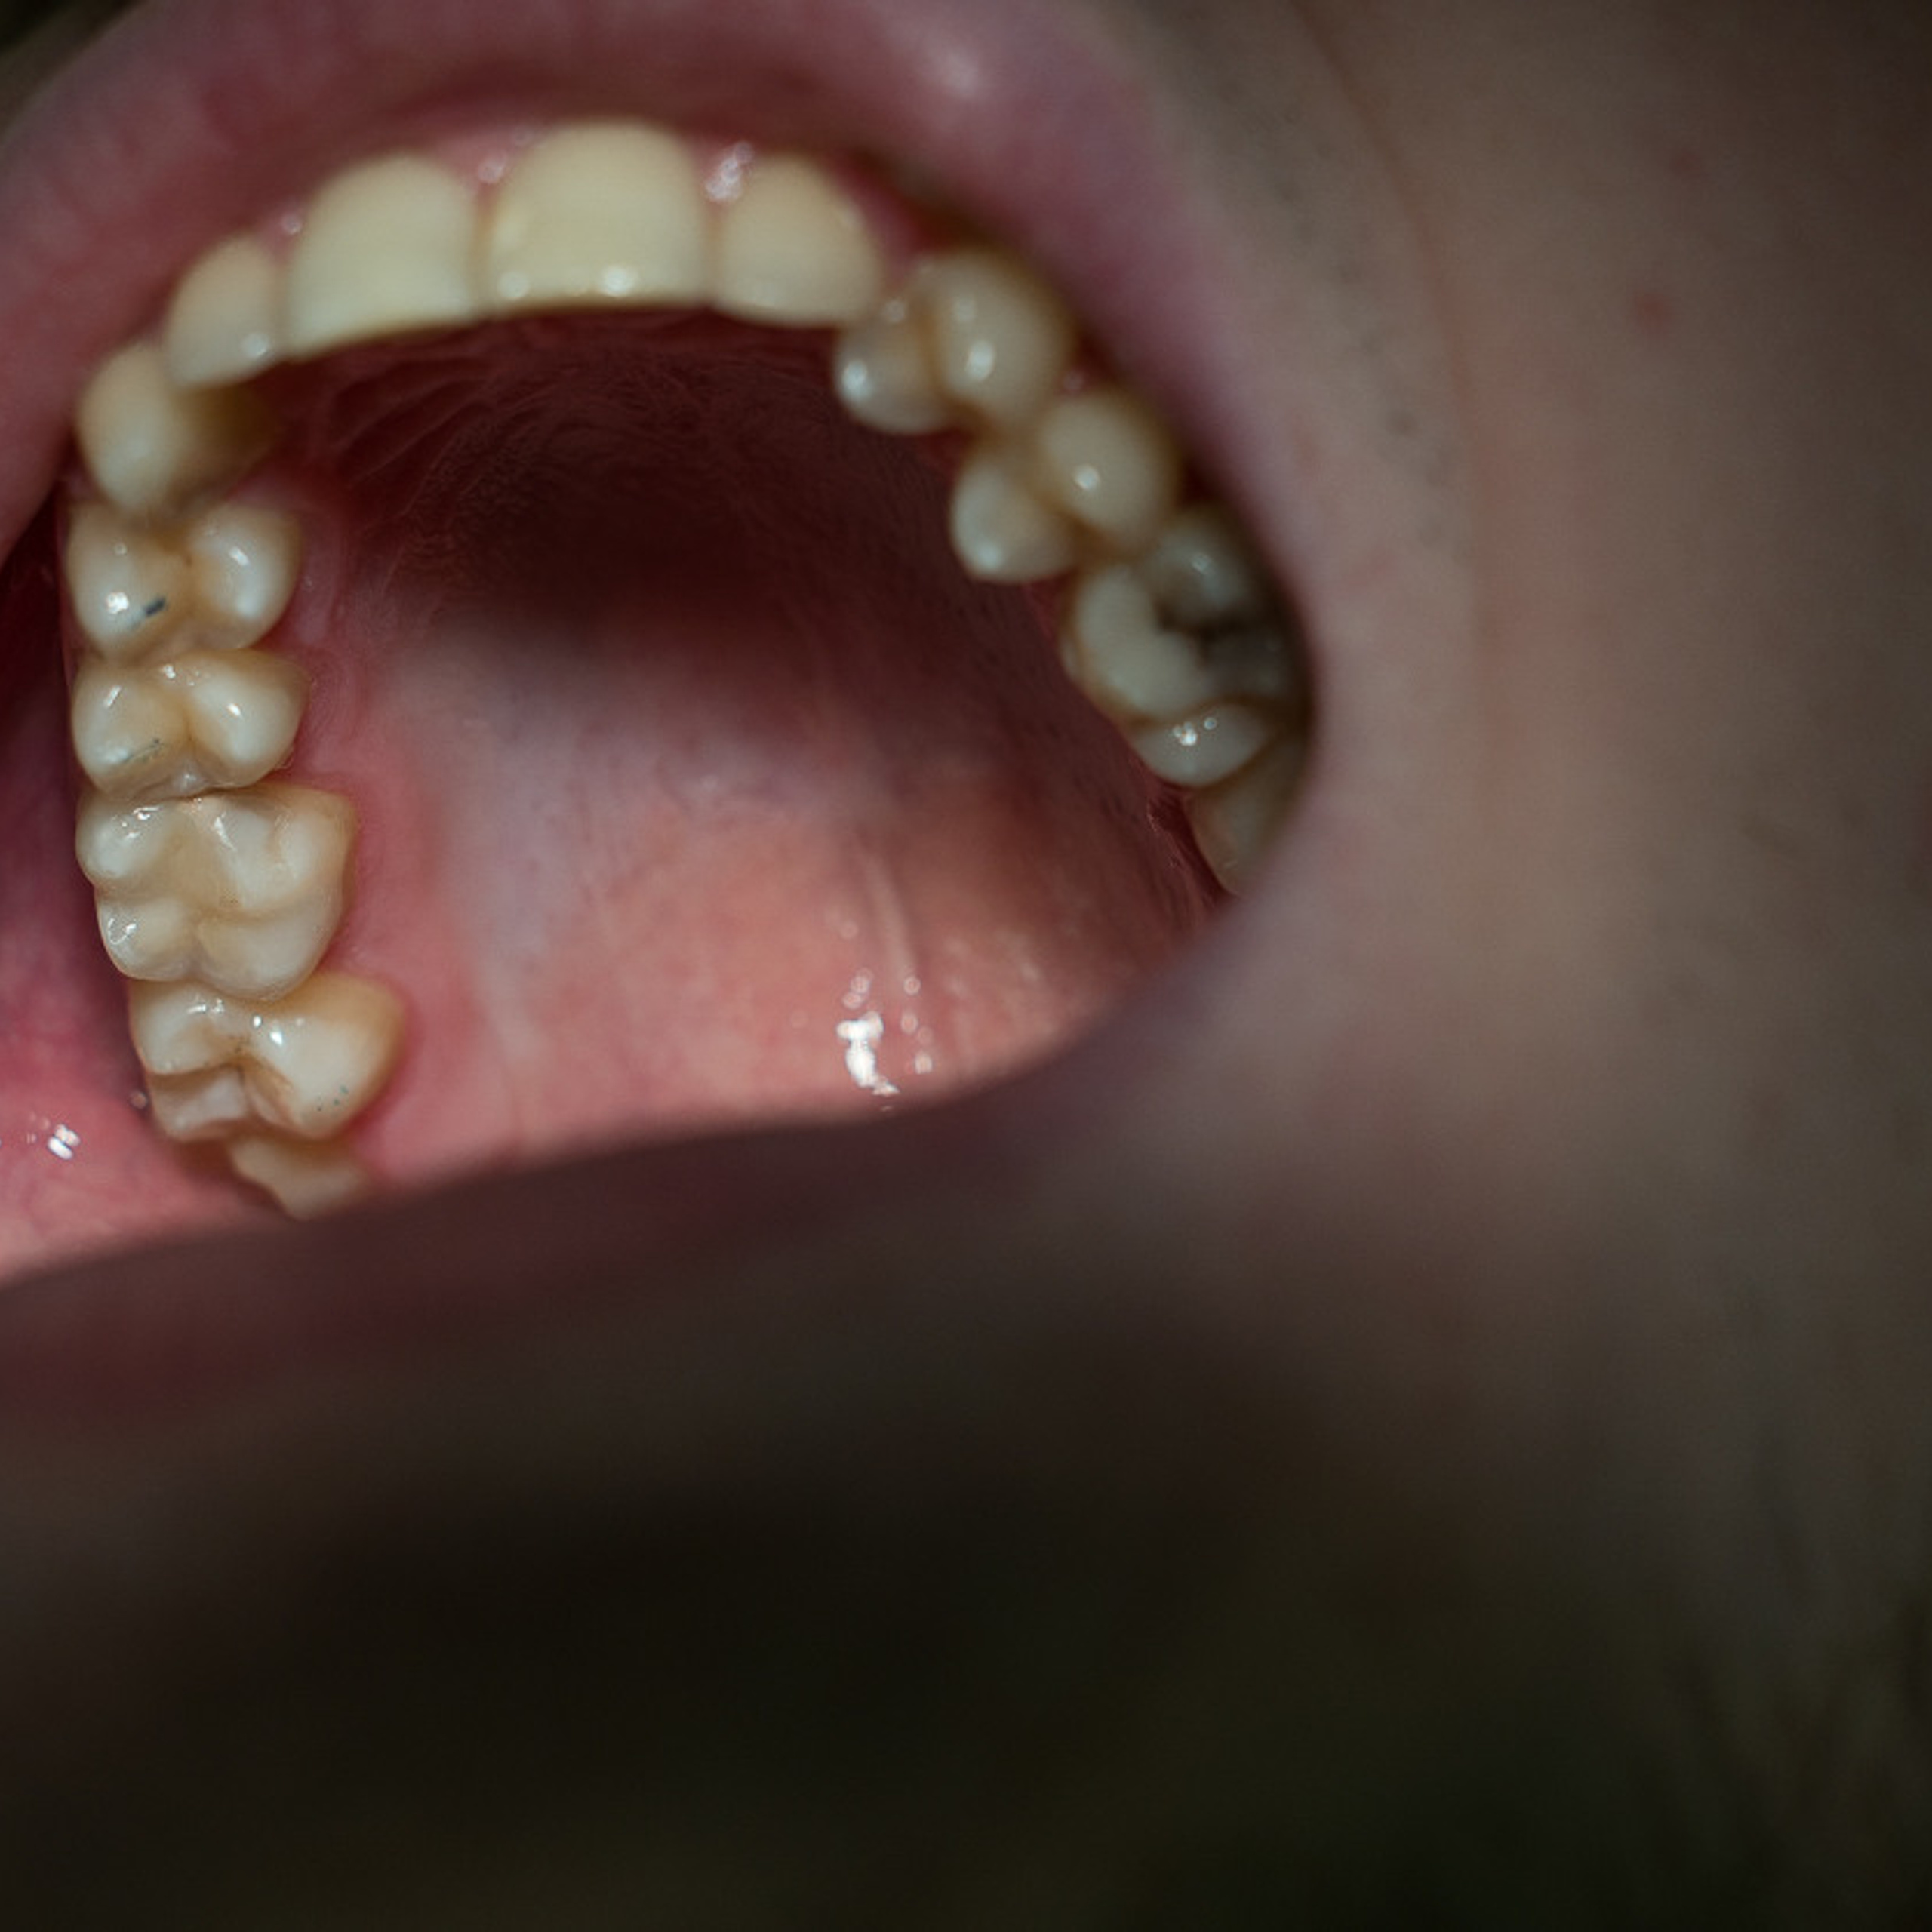

Фотографии учеников до обучения